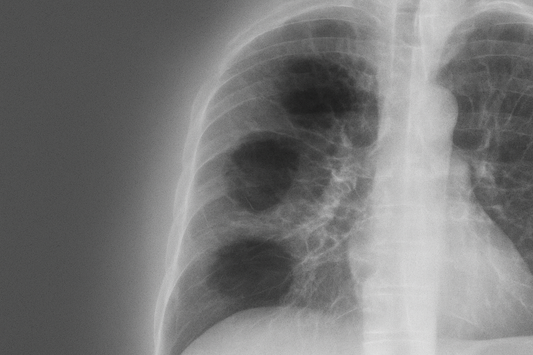

Sarcoidosis and the Lungs: Understanding a Systemic Condition with Respiratory Impact

Sarcoidosis is a rare inflammatory disease that can affect multiple organs, but it most commonly involves the lungs and lymph nodes. While the exact cause remains unknown, the condition results...